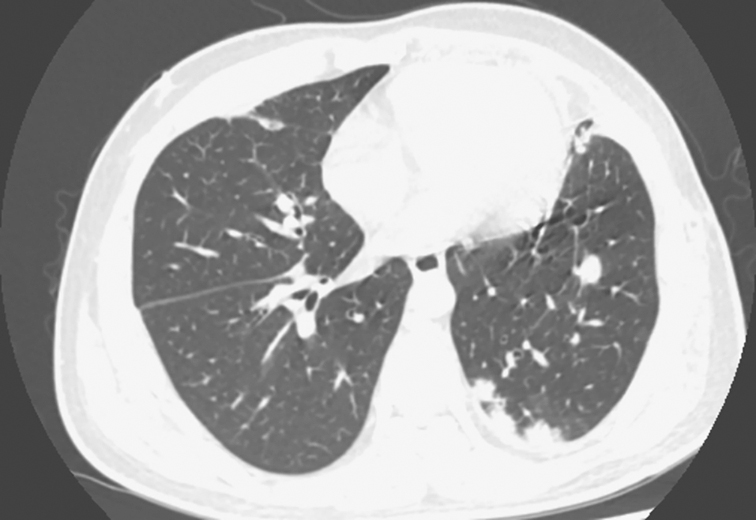

2014年8月6日胸部CT:左肺上叶支气管呈术后改变,支气管残端显示不清。左上叶前段可见大片状密度增高影,边缘模糊,平扫CT值46HU,增强后CT值73HU。双肺野内和胸膜下可见散在大小不等结节状密度增高影,边缘模糊,较大者位于右下叶背段,大小约2.4cm×1.8cm,气管、支气管通畅,纵隔内可见多个小淋巴结,较大者直径8mm。无胸腔积液征象(图1、图2)

图2 发病第3个月胸部CT表现

胸部CT可见双肺多发结节灶